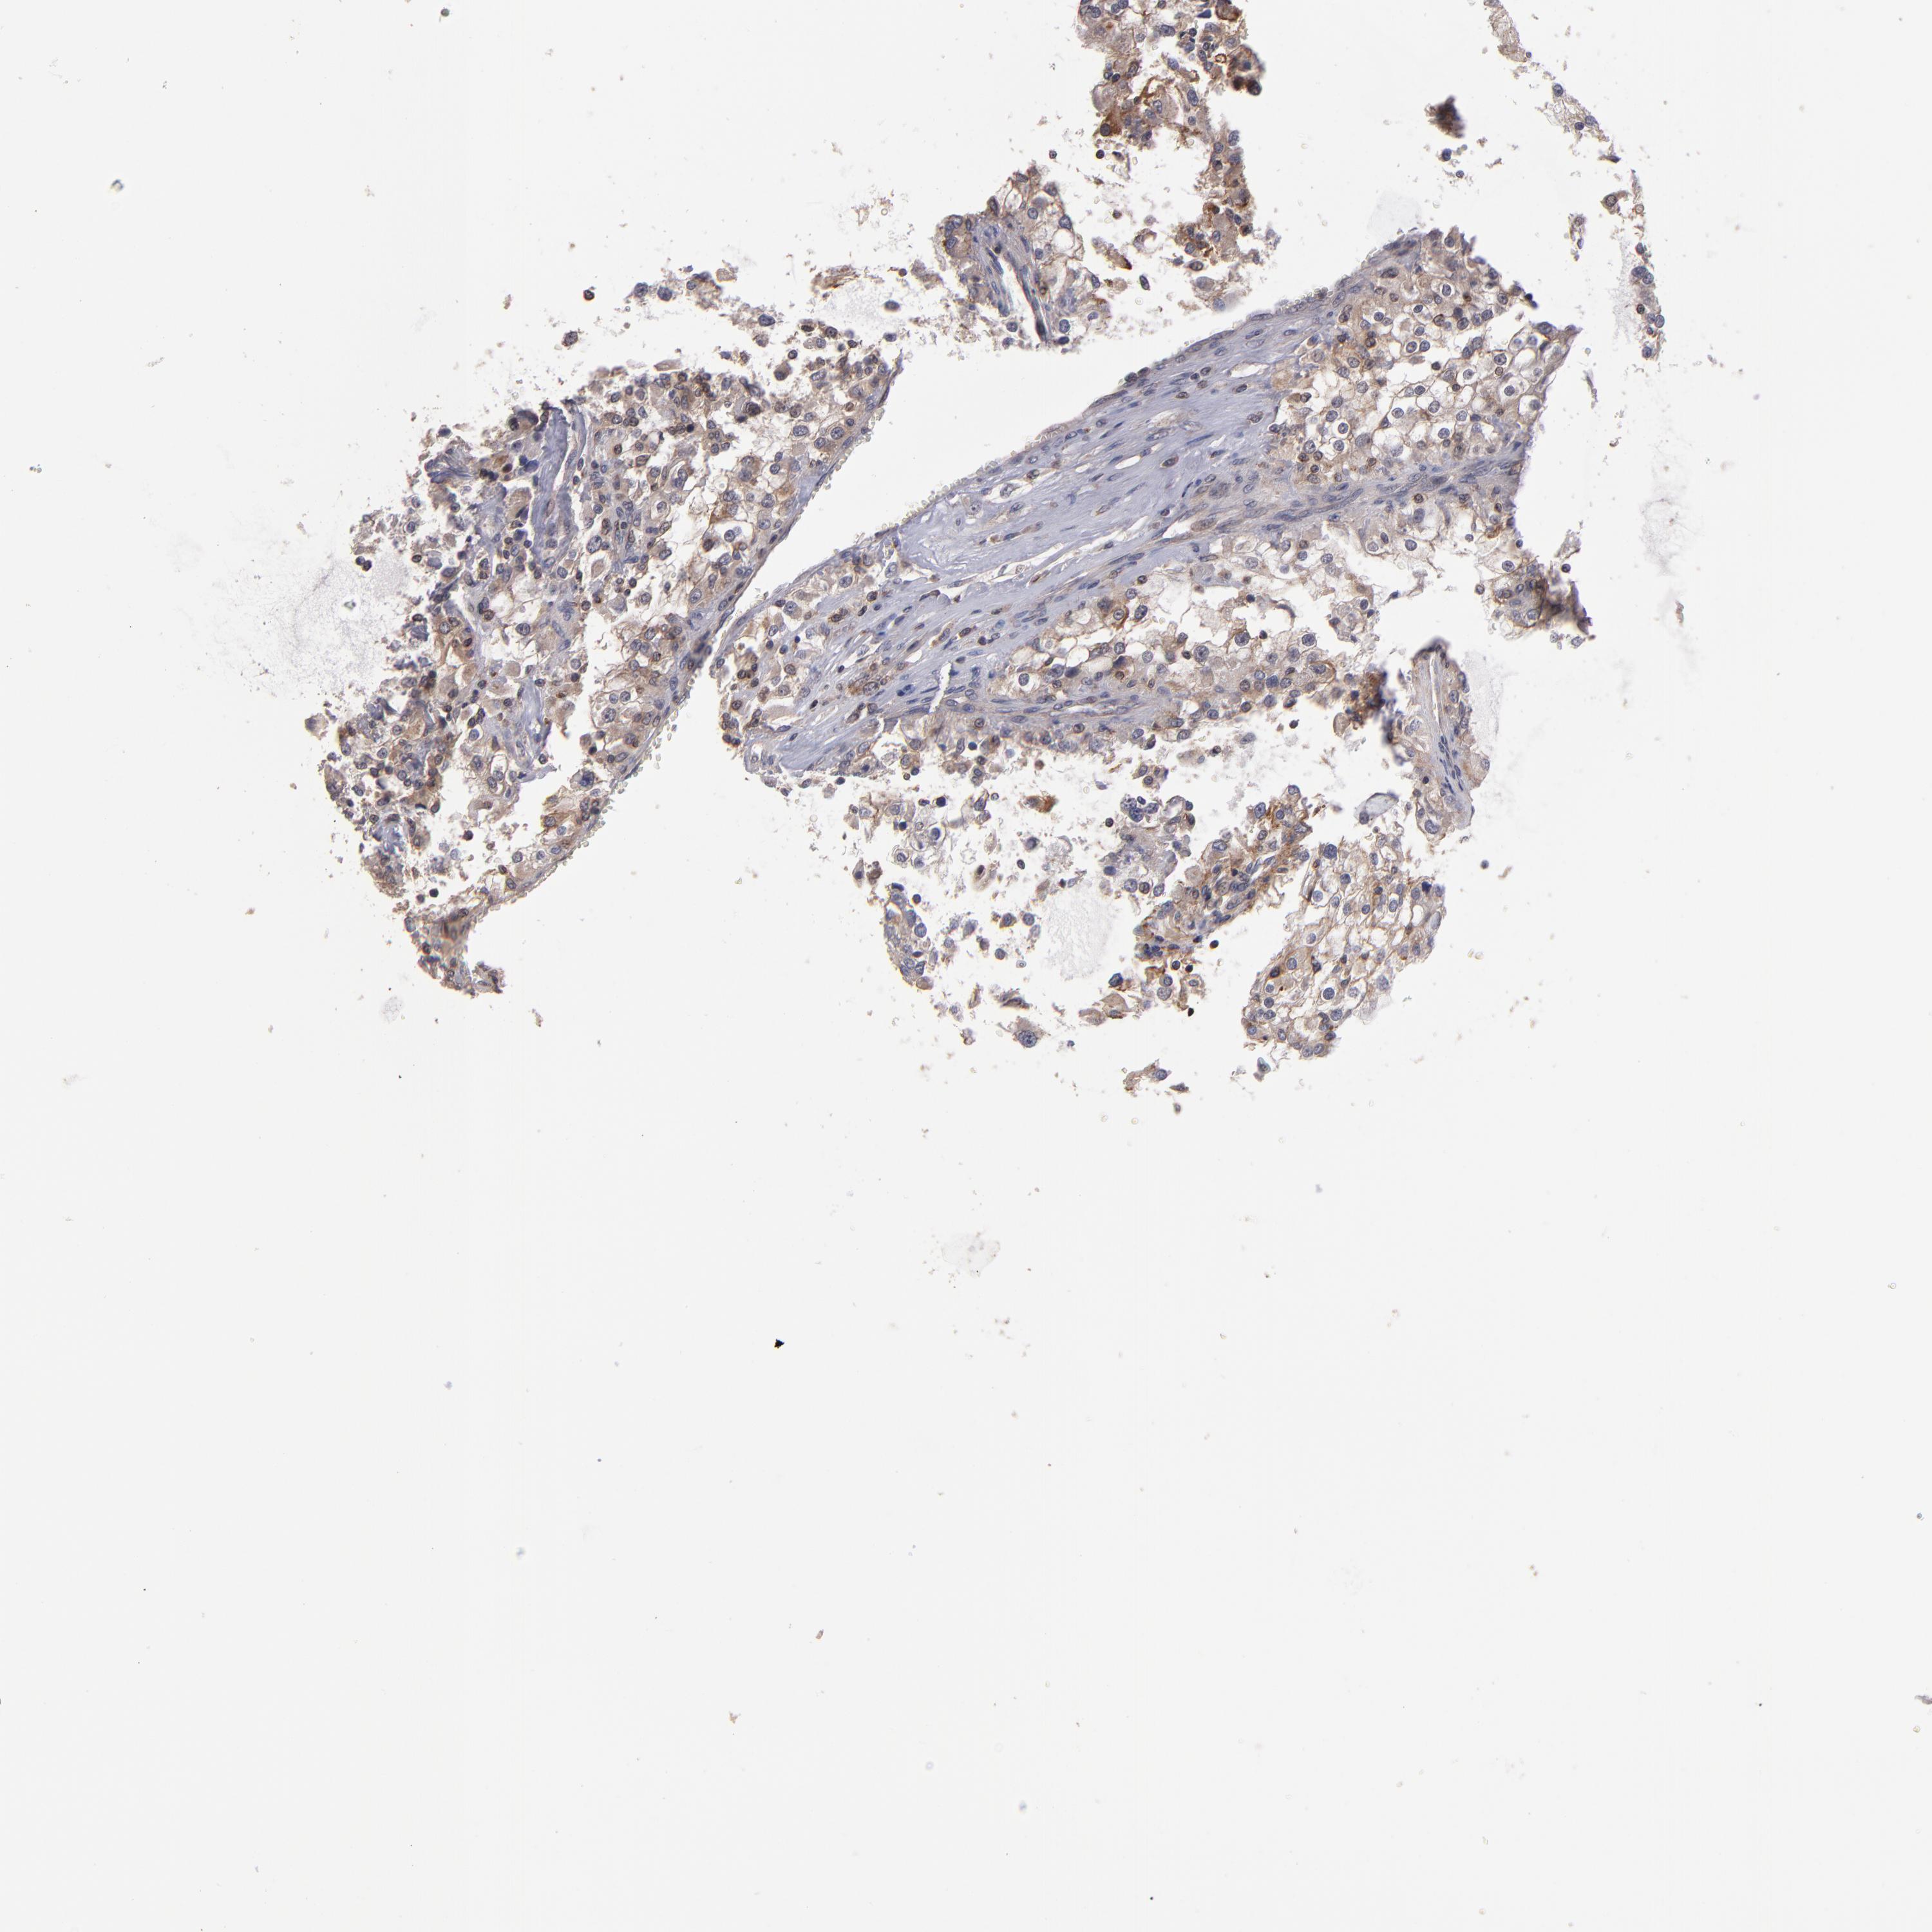

KIDNEY RENAL CLEAR CELL CARCINOMA (VALIDATION) - Interactive survival scatter ploti

The Survival Scatter plot shows the clinical status (i.e. dead or alive) for all individuals in the patient cohort, based on the same data that underlies the corresponding Kaplan-Meier plots. Patients that are alive at last time for follow-up are shown in blue and patients who have died during the study are shown in red.

& Survival analysisi

Kaplan-Meier plots summarize results from analysis of correlation between mRNA expression level and patient survival. Patients were divided based on level of expression into one of the two groups "low" (under cut off) or "high" (over cut off). X-axis shows time for survival (years) and y-axis shows the probability of survival, where 1.0 corresponds to 100 percent.

NF2 is not prognostic in Kidney Renal Clear Cell Carcinoma (validation)

Best expression cut offi

Based on the FPKM value of each gene, patients were classified into two groups and association between prognosis (survival) and gene expression (FPKM) was examined. The best expression cut-off refers the FPKM value that yields maximal difference with regard to survival between the two groups at the lowest log-rank P-value. Best expression cut-off was selected based on survival analysis .

When clicking on this number, the vertical dashed line indicating cut-off, the interactive survival plot, and the Kaplan-Meier curve will be adjusted to show results based on the best expression cut-off.

: 12.26

Average pTPM 13.8

Number of samples 100